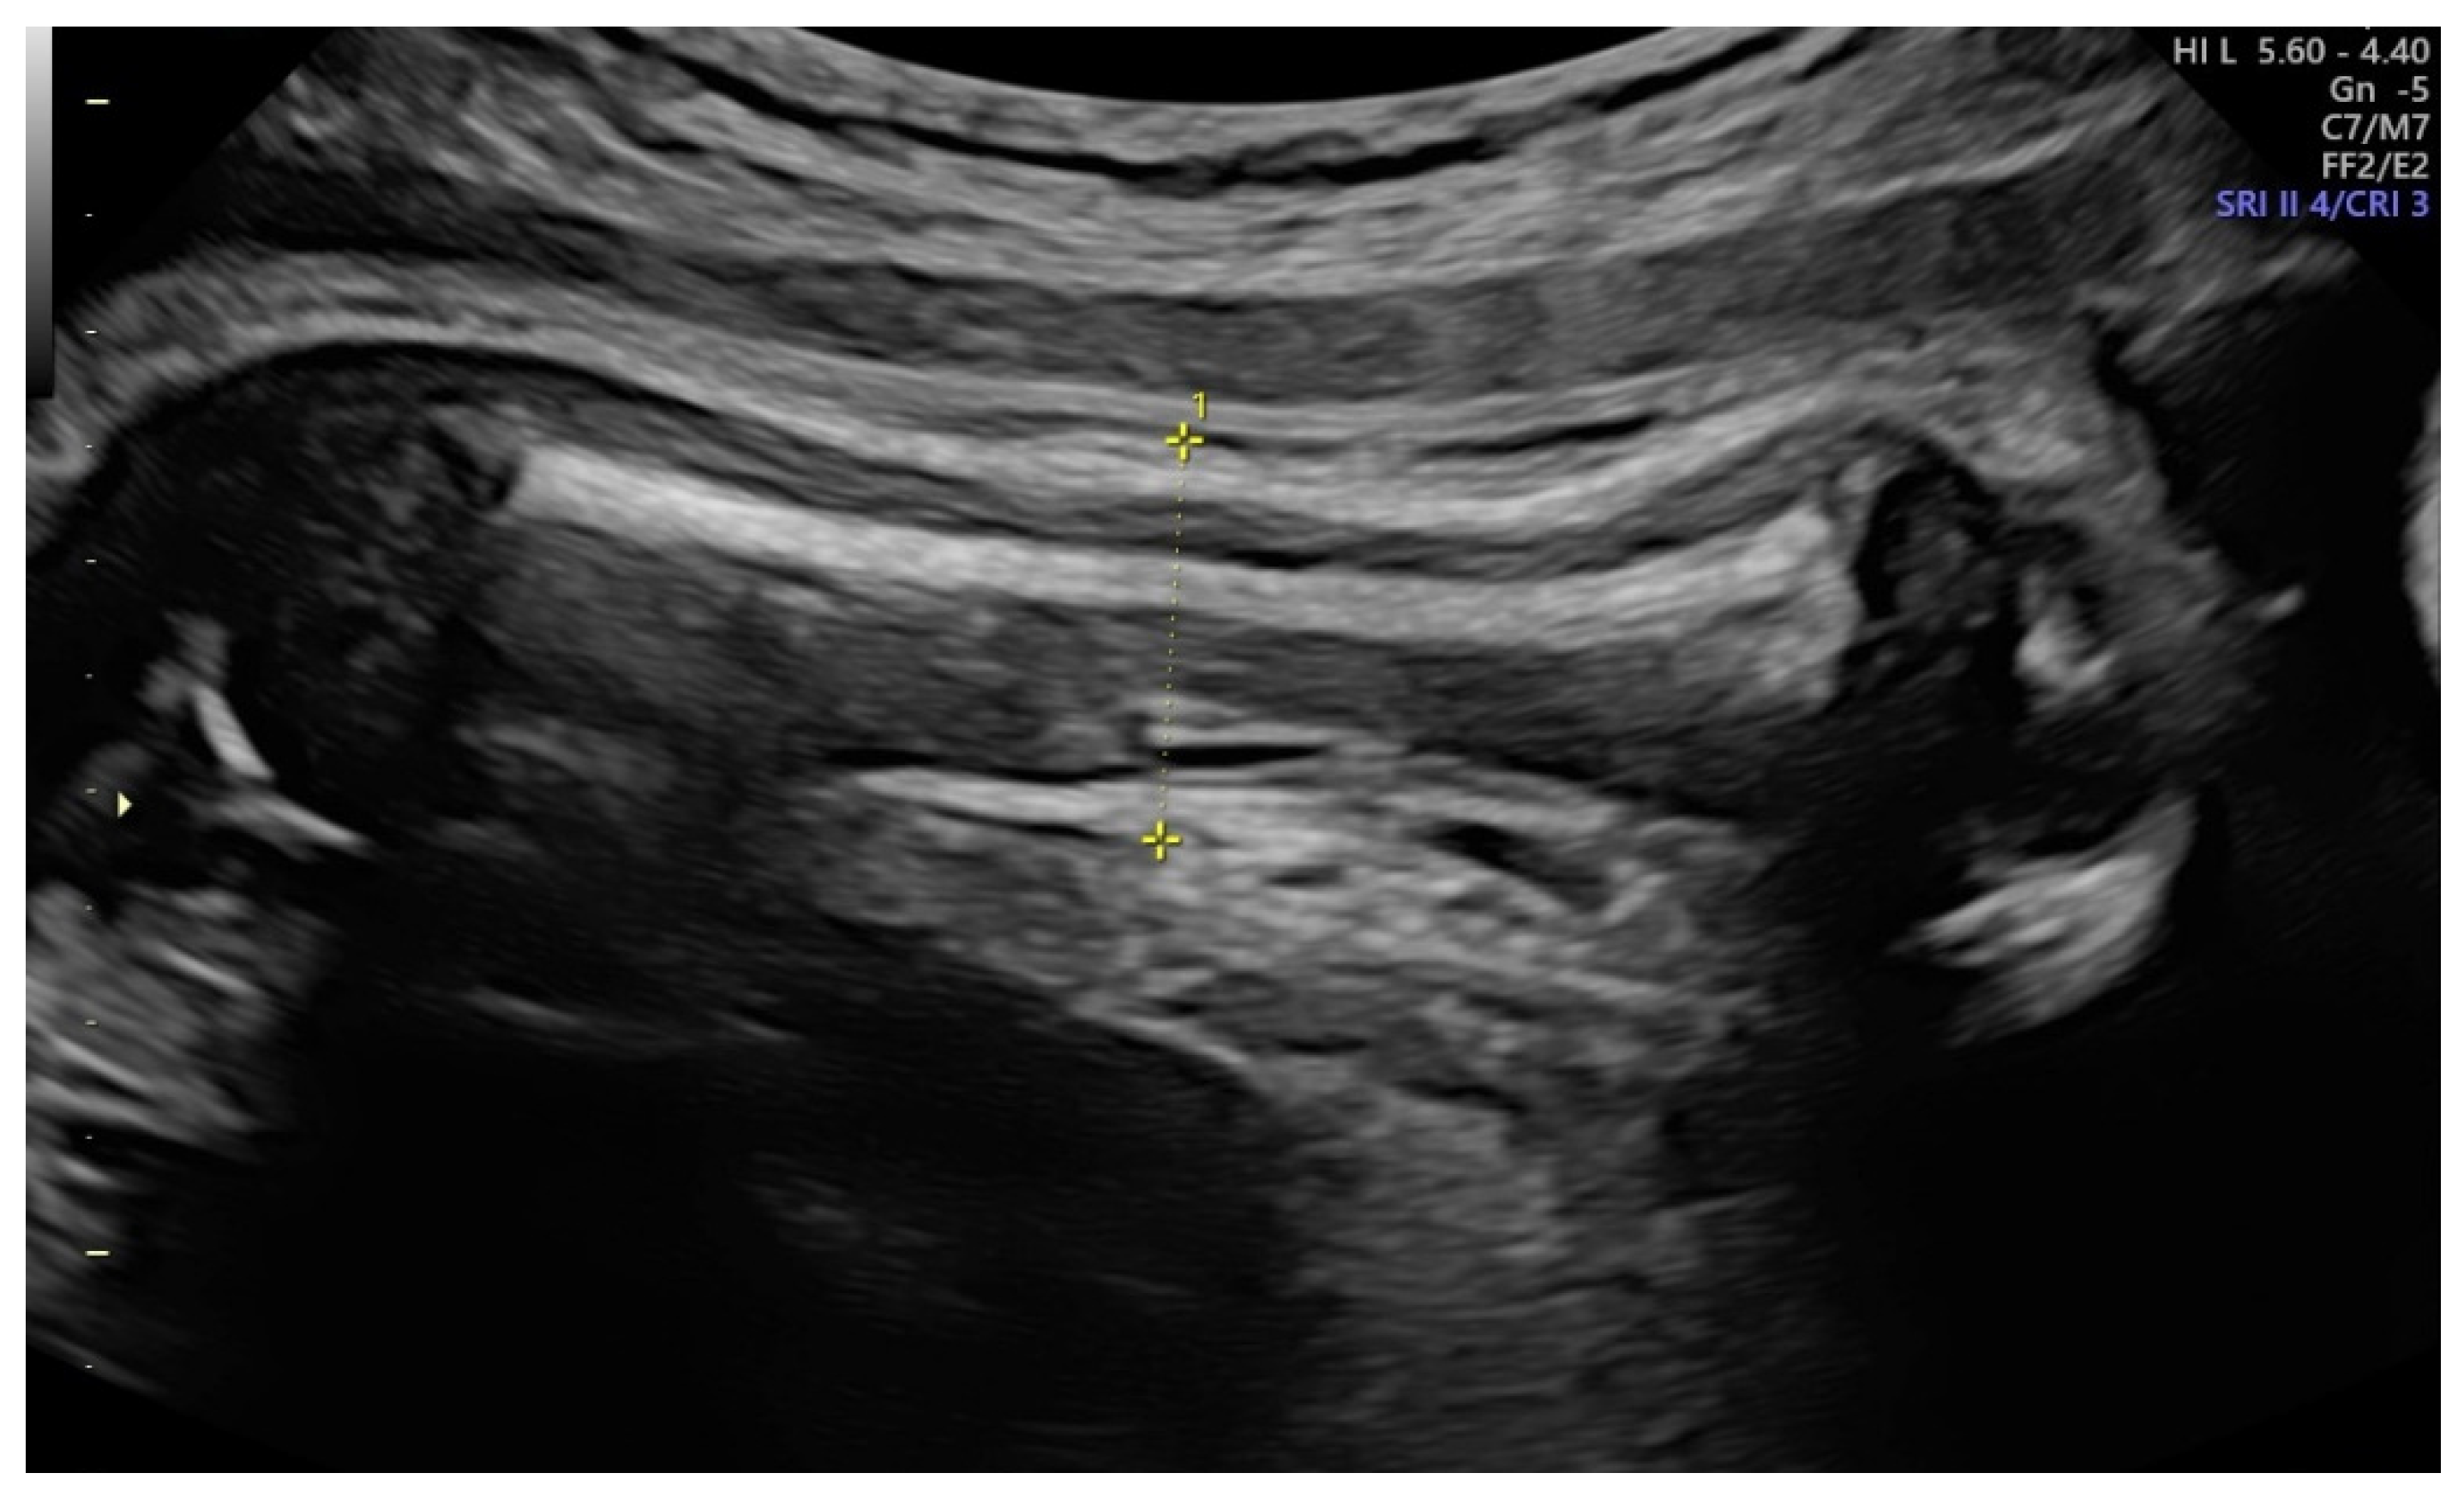

Accuracy of Fetal Biacromial Diameter and Derived Ultrasonographic Parameters to Predict Shoulder Dystocia: A Prospective Observational Study

2. Materials and Methods